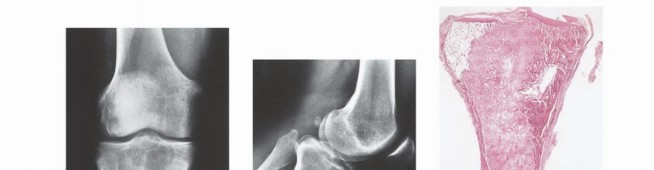

Enneking also established a robust staging system for benign osseous lesions based on clinical presentation and radiographic behavior:

* Stage 1 (Latent): Asymptomatic, discovered incidentally. Static growth or spontaneous healing. Thick, well-defined reactive sclerotic rim. Treated with observation or simple curettage (e.g., Non-ossifying fibroma).

* Stage 2 (Active): Progressive growth, mild symptoms, but contained within natural cortical barriers. Treated with extended curettage and burr drilling (e.g., Aneurysmal bone cyst).

* Stage 3 (Aggressive): Rapid growth, symptomatic, destroys cortical bone, and extends into soft tissue. Minimal to no reactive bone rim. Requires aggressive extended curettage with local adjuvants (liquid nitrogen, phenol, argon beam) or wide en bloc resection (e.g., Giant cell tumor of bone).

Imaging Set 1: Pathophysiology and Staging Fundamentals